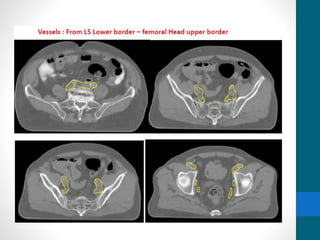

Contouring Vessels

• From L5 Lower border – femoral Head upper border

Contouring Vessels • FromL5 Lower border – femoral Head upper border • CTV Nodal • Vessels + 0.7mm margin • Presacral 10mm brush • Obturator 18mm • CTV Nodal+CTV Primary = CTV Combined • CTV Combined + 1cm = PTV